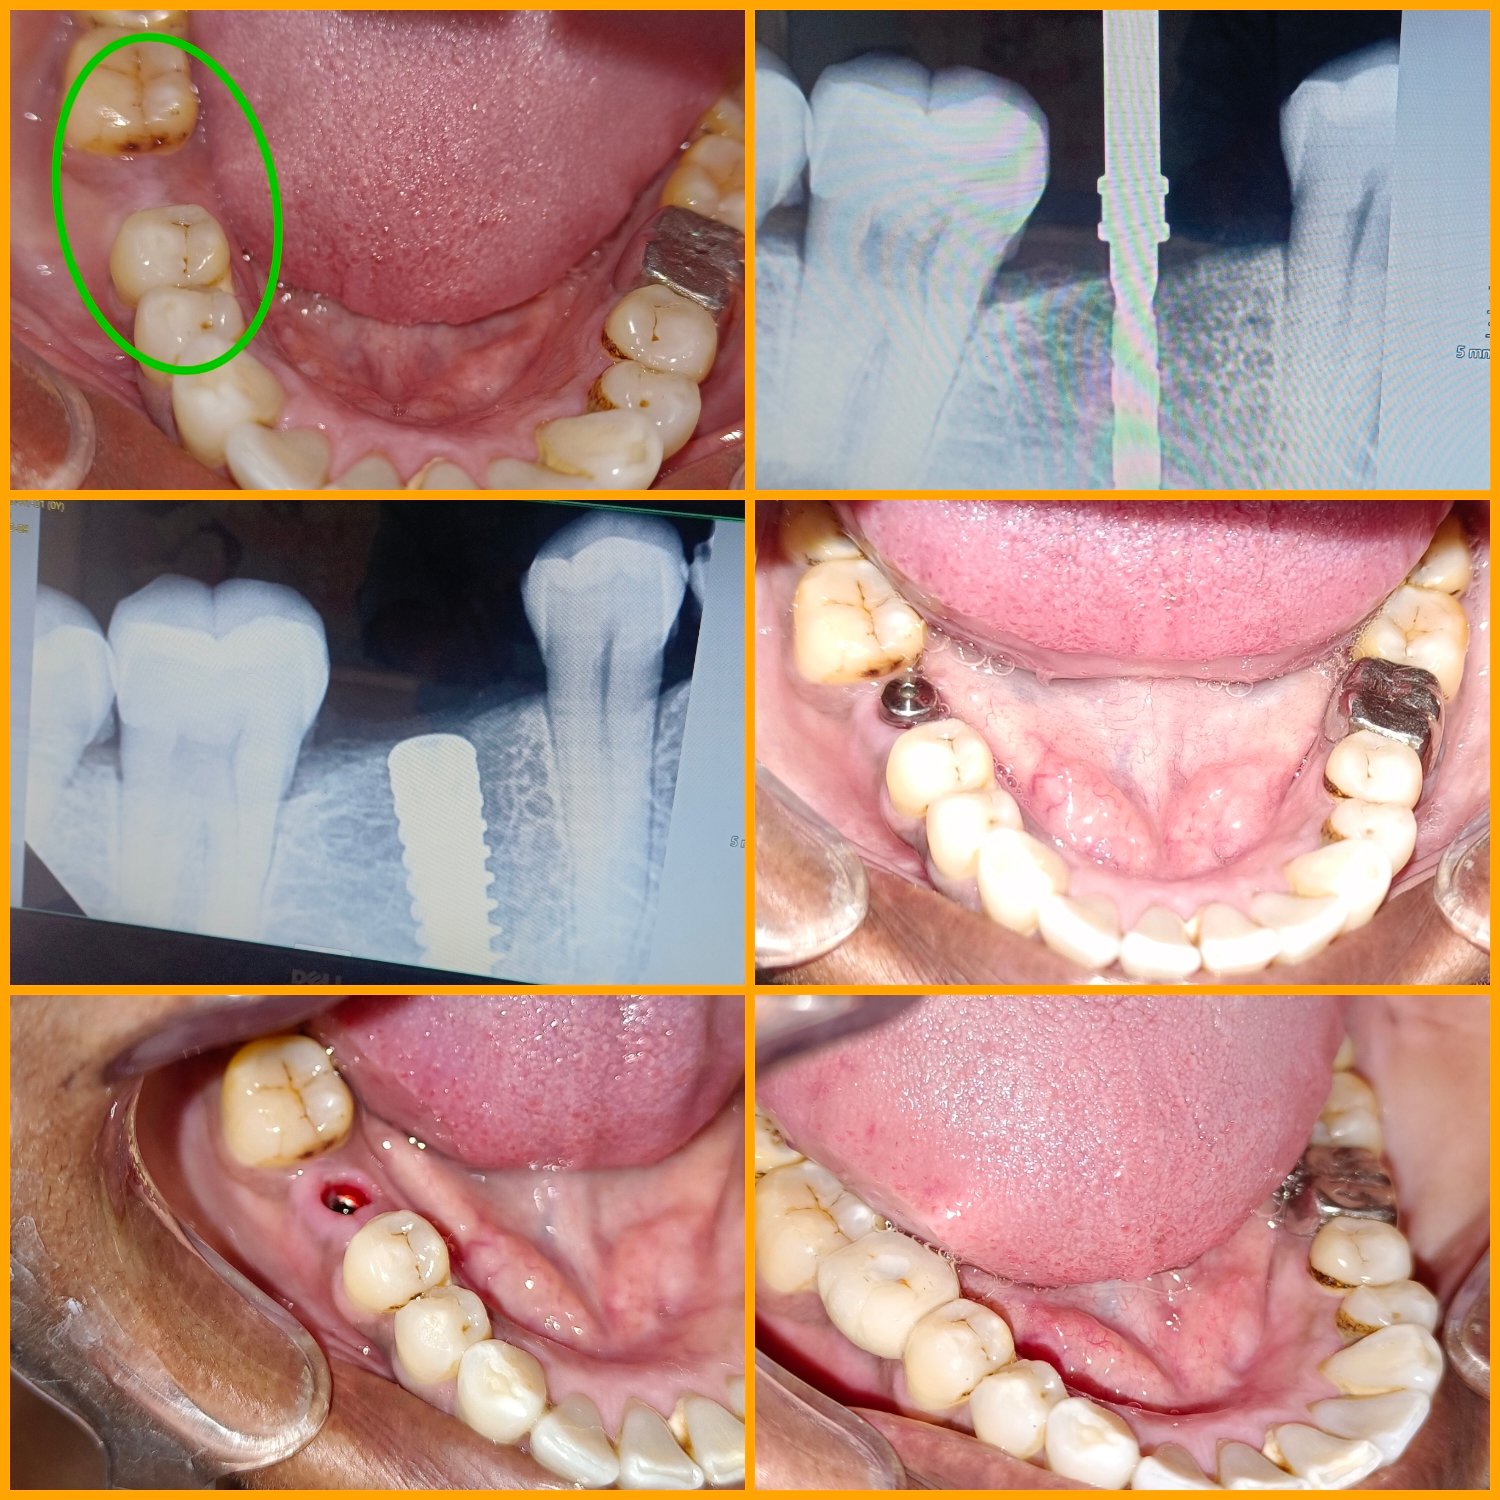

ЁЯПе рдзрд╛рд░рд╛рд╢рд┐рд╡ рдЬрд┐рд▓реНрд╣реНрдпрд╛рддреАрд▓ рдкреНрд░рд╕рд┐рджреНрдз рдбреЗрдВрдЯрд▓ рд╣реЙрд╕реНрдкрд┐рдЯрд▓ & рдлреЗрд╢рд┐рдпрд▓ рдЯреНрд░реЙрдорд╛ рдХреЗрдЕрд░ рд╡ рдЗрдореНрдкреНрд▓рд╛рдВрдЯ рд╕реЗрдВрдЯрд░ ЁЯПе ЁЯПердЕрддреНрдпрд╛рдзреБрдирд┐рдХ рдбрд┐рдЬрд┐рдЯрд▓ рдПрдХреНрд╕-рд░реЗ ЁЯПердЗрдВрдЯреНрд░рд╛ рдУрд░рд▓ рдХреЕрдореЗрд░рд╛ рджреНрд╡рд╛рд░реЗ рддрдкрд╛рд╕рдгреА ЁЯж╖рдЕрд▓реНрдЯреНрд░рд╛рд╕реЛрдирд┐рдХ рдорд╢реАрдирджреНрд╡рд╛рд░реЗ рджрд╛рдд рд╕рд╛рдл рдХрд░рдгреЗ ЁЯж╖рдХреГрддреНрд░рд┐рдо рджрдВрддрд░реЛрдкрдг ЁЯж╖рдЕрдХреНрдХрд▓рджрд╛рдбреЗ рд╡рд░реАрд▓ рд╢рд╕реНрддреНрд░рдХреНрд░рд┐рдпрд╛ ЁЯж╖рдЬрдмрдбреНрдпрд╛рдВрдЪреЗ рдлреНрд░реЕрдХреНрдЪрд░ рд╡рд░реАрд▓ рд╢рд╕реНрддреНрд░рдХреНрд░рд┐рдпрд╛ ЁЯзмрдЕрддреНрдпрд╛рдзреБрдирд┐рдХ рдкрджреНрдзрддреАрдиреЗ рджрд╛рддрд╛рдВрдЪреНрдпрд╛ рдирд╕рд╛ рд╡рд░реАрд▓ рдЙрдкрдЪрд╛рд░ ЁЯзмрддреЛрдВрдбрд╛рддреАрд▓ рдореМрдЦрд┐рдХ рд╢рд╕реНрддреНрд░рдХреНрд░рд┐рдпрд╛ ЁЯзмрд╕рдВрдкреВрд░реНрдг рдХрд┐рдВрд╡рд╛ рдЕрдВрд╢рддрдГ рдХрд╡рд│реА рдмрд╕рд╡рдгреЗ ЁЯзмрд╡реЗрдбреЗрд╡рд╛рдХрдбреЗ рджрд╛рдд рд╕рд░рд│ рдХрд░рдгреЗ

ЁЯПе рдлреЗрд╢рд┐рдпрд▓ рдЯреНрд░реЙрдорд╛ рдХреЗрдЕрд░ рд╡ рдЗрдореНрдкреНрд▓реЗрдВрдЯ рд╕реЗрдВрдЯрд░

ЁЯПе рд╕реНрдХреНрд░реВ рдЪреНрдпрд╛ рд╕рд╛рд╣реНрдпрд╛рдиреЗ рдлрд┐рдХреНрд╕ рджрд╛рдд рдмрд╕рд╡рдгреЗ